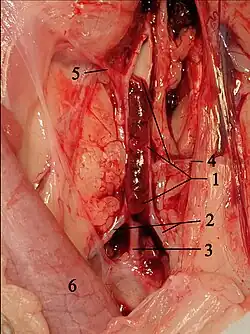

Surgical septal myectomy

Surgical septal myectomy is an open-heart operation done to relieve symptoms in people who remain severely symptomatic despite medical therapy. It has been performed successfully since the early 1960s.[20] Surgical septal myectomy uniformly decreases left ventricular outflow tract obstruction and improves symptoms, and in experienced centers has a surgical mortality of less than 1%, as well as 85% success rate.[40] It involves a median sternotomy (general anesthesia, opening the chest, and cardiopulmonary bypass) and removing a portion of the interventricular septum.[15] Surgical myectomy resection that focuses just on the subaortic septum, to increase the size of the outflow tract to reduce Venturi forces, may be inadequate to abolish systolic anterior motion (SAM) of the anterior leaflet of the mitral valve. With this limited resection, the residual mid-septal bulge still redirects flow posteriorly; SAM persists because flow still gets behind the mitral valve. It is only when the deeper portion of the septal bulge is resected that flow is redirected anteriorly away from the mitral valve, abolishing SAM. With this in mind, a modification of the Morrow myectomy termed extended myectomy, mobilization and partial excision of the papillary muscles has become the excision of choice.[54][55][56][57] In people with particularly large redundant mitral valves, anterior leaflet plication may be added to complete separation of the mitral valve and outflow.[57] Complications of septal myectomy surgery include possible death, arrhythmias, infection, incessant bleeding, septal perforation/defect, and stroke.[40]

Alcohol septal ablation

Alcohol septal ablation, introduced by Ulrich Sigwart in 1994, is a percutaneous technique that involves an injection of alcohol into one or more septal branches of the left anterior descending artery. This is a catheter technique with results similar to the surgical septal myectomy procedure but is less invasive since it does not involve general anesthesia and opening of the chest wall and pericardium (which are done in a septal myectomy). In a select population with symptoms secondary to a high outflow tract gradient, alcohol septal ablation can reduce the symptoms of HCM. In addition, older individuals and those with other medical problems, for whom surgical myectomy would pose an increased procedural risk, would likely benefit from the less-invasive septal ablation procedure.[15][58]

When performed properly, an alcohol septal ablation induces a controlled heart attack, in which the portion of the interventricular septum that involves the left ventricular outflow tract is infarcted and will contract into a scar. There is debate over which people are best served by surgical myectomy, alcohol septal ablation, or medical therapy.[59]